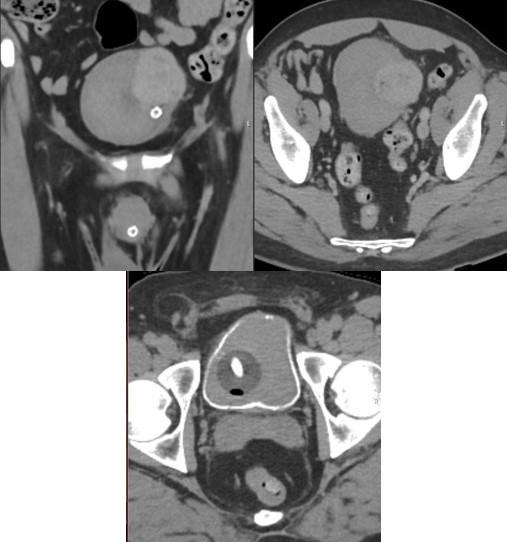

A fifty-nine-year-old male with no significant past medical history was admitted through accident and emergency to the referring hospital with acute clot retention. Initial conservative management with manual bladder washouts and continuous bladder irrigation, via three-way catheter, was unsuccessful, with ongoing transfusion dependent haematuria. An urgent CT urogram showed a solid 8 cm bladder mass and extensive intravesical clots (Figure 1).

Figure 1: (A) coronal view of non-contrast CT-KUB with solid looking mass in the left bladder wall and bladder full of clots. (B) Axial view of non-contrast CT scan showing same bladder mass with bladder full of clots. (C) Axial view of delayed excretory phase CT urogram showing rim of contrast surrounding large bladder clot.